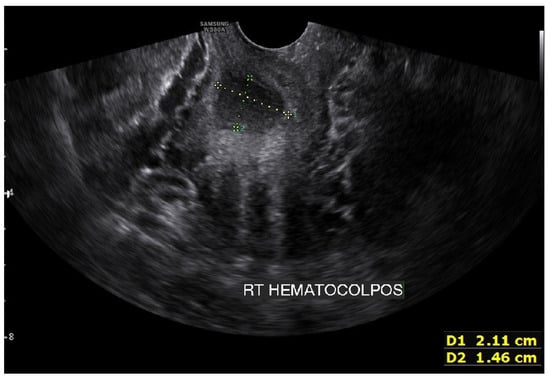

Figure 4. Transvaginal ultrasonogram image showing approximately 21 mm × 15 mm of fluid collection in the right side obstructed hemivagina. This suggested hematocolpos on the right side was too small and made it difficult to operate on the first visit.

On the abdominopelvic CT image taken at the ER, we noticed she had HWW syndrome (right side hemi-vagina and right kidney agenesis) with acute pyelonephritis (APN) of the left kkidne (Figure 3a,b). After admission, transvaginal USG (Figure 4) and pelvic MRI (Figure 5a–c) were performed. We planned to perform the vaginal wall resection surgery on the next menstrual period as she needed antibiotics treatment for the APN, and the amount of hematocolpos was not so extensive that we could not clearly identify the bulging vaginal wall.